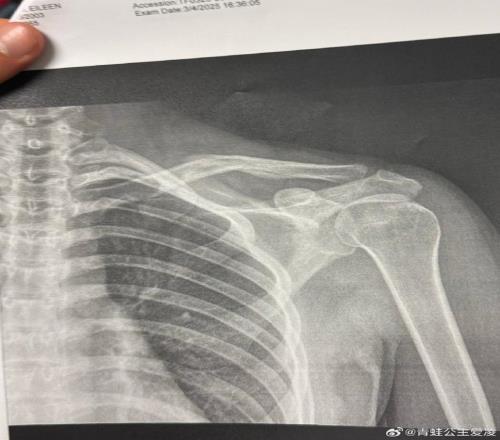

2025年3月9日,谷爱凌在社交网络上发布了一张X光片。

但事实是,谷爱凌确实在这个奥运周期的最后冲刺阶段不停经历着伤病的折磨。2025年3月9日,谷爱凌在社交网络上发布了一张X光片。图片上,她右侧锁骨的裂缝清晰可见,配文只有一个心碎的表情符号,而这仅仅是“职业生涯最艰难一年”的开始。